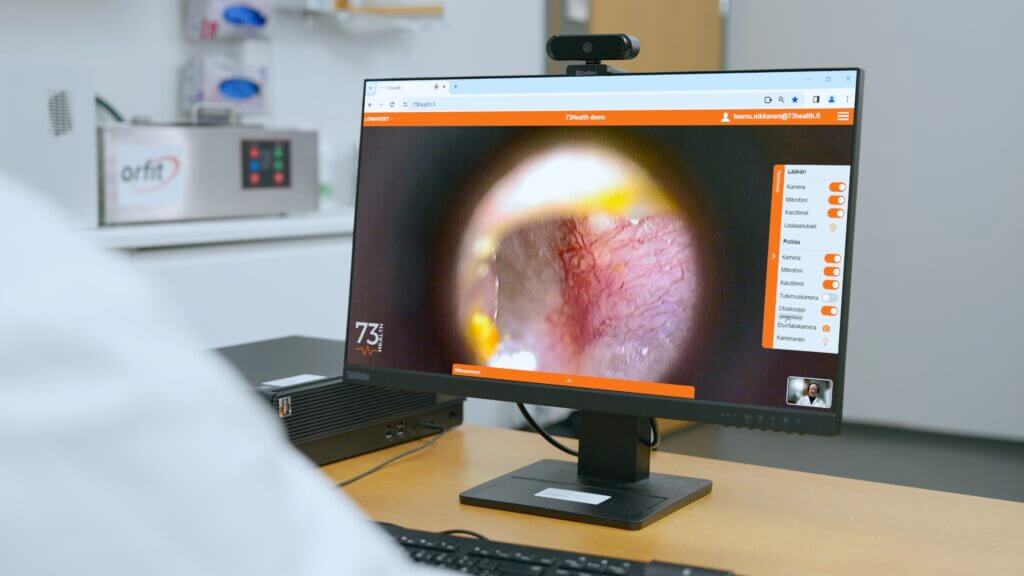

Step 2: The Physical Examination

Guided by your doctor, a trained assistant will use the eEVA™ device to perform the physical examination.

Yes. The eEVA™ device provides doctors with the same clinical data they would gather in a traditional examination, including real-time heart and lung sounds and high-quality visual data, ensuring an accurate and reliable diagnosis.

Our eEVA™ device supports Cardiology (digital stethoscope), Dermatology (high-resolution camera), Pulmonology (lung sound analysis), and ENT (otoscope). More specialties including Ophthalmology and General Medicine are available via video consultation.

What is eEVA™ and is it certified?

eEVA™ (electronic EVAluation) is a compact telehealth diagnostic device developed by Finland-based 73Health. CARELINE holds DRAP Import Licence No. ELI-EN00000073, certifying it as a safe and compliant medical device for use in Pakistan.